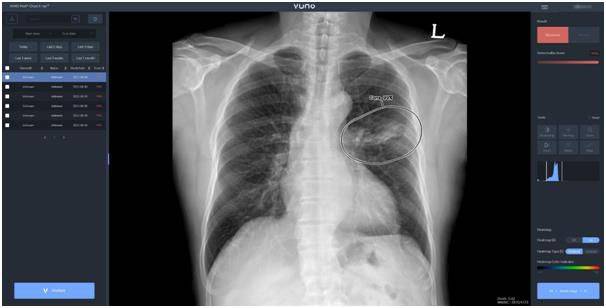

뷰노메드 체스트 엑스레이는 인공지능(AI) 기반 흉부 엑스레이 영상 판독 솔루션이다. 뷰노는 지난 6월 같은 제품을 삼성전자의 이동형 촬영 장비 ‘GM85′에 공급하는 계약을 체결했다. 이동형에 이어 천장형으로 탑재 제품을 확대했다.

뷰노는 이를 통해 글로벌 디지털 엑스레이 시장을 공략한다는 계획이다. 세계 의료기기 기업과 뷰노메드 솔루션을 탑재하는 협력관계를 구축한다는 것이다.뷰노메드 체스트 엑스레이는 폐 질환 진단을 돕는 AI 솔루션이다. 흉부 엑스레이 이상소견을 탐지하고 위치와 소견을 제시한다. 2019년 8월 식품의약품안전처의 허가를 받았다.

지난해 6월에는 유럽 제품인증(CE)을 획득해 국내 및 주요 유럽 국가에 판매 중이다.회사에 따르면 뷰노메드 체스트 엑스레이는 AI 알고리즘의 연산 최적화로 장비를 경량화한다. 이로 인해 다양한 엑스레이 장비에 탑재할 수 있다.